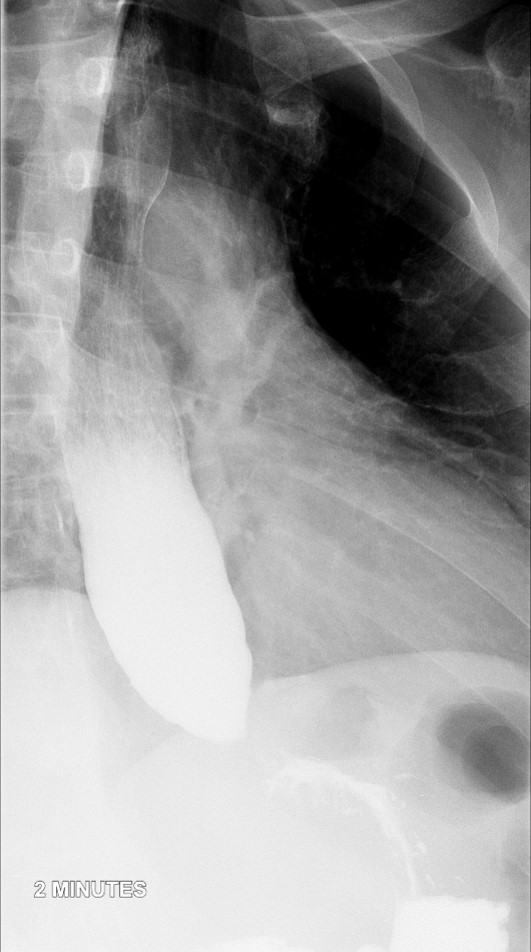

- Method:

- Place the patient in an upright LPO under the fluoroscope.

- Have the patient swallow the barium a period of 15 - 20 seconds.

- Obtain spot radiographs of the distal esophagus at 1, 2, and 5 minutes after ingestion of the barium

(key image 1)

(key image 2)

(key image 3).

- Ensure the distance between the patient and the fluoroscope is kept constant between all 3 radiographs.

- If the barium contrast material completely clears the esophagus at 1 or 2 minutes, do not take the subsequent spot images.

- If all contrast material has emptied from the thoracic esophagus the study is negative, proceed with a regular thoracic barium swallow.

- If contrast material remains in the thoracic esophagus, have the patient take some additional sips of thin barium obtaining images of the gastroesophageal junction as contrast material passes through it.

- Images are obtained in the upright LPO projection.

- Films are obtained 1 minute, 2 minutes, and 5 minutes after contrast material administration.

- If contrast has emptied from the thoracic esophagus on the one minute image, the 2 minute and 5 minute images are not needed.